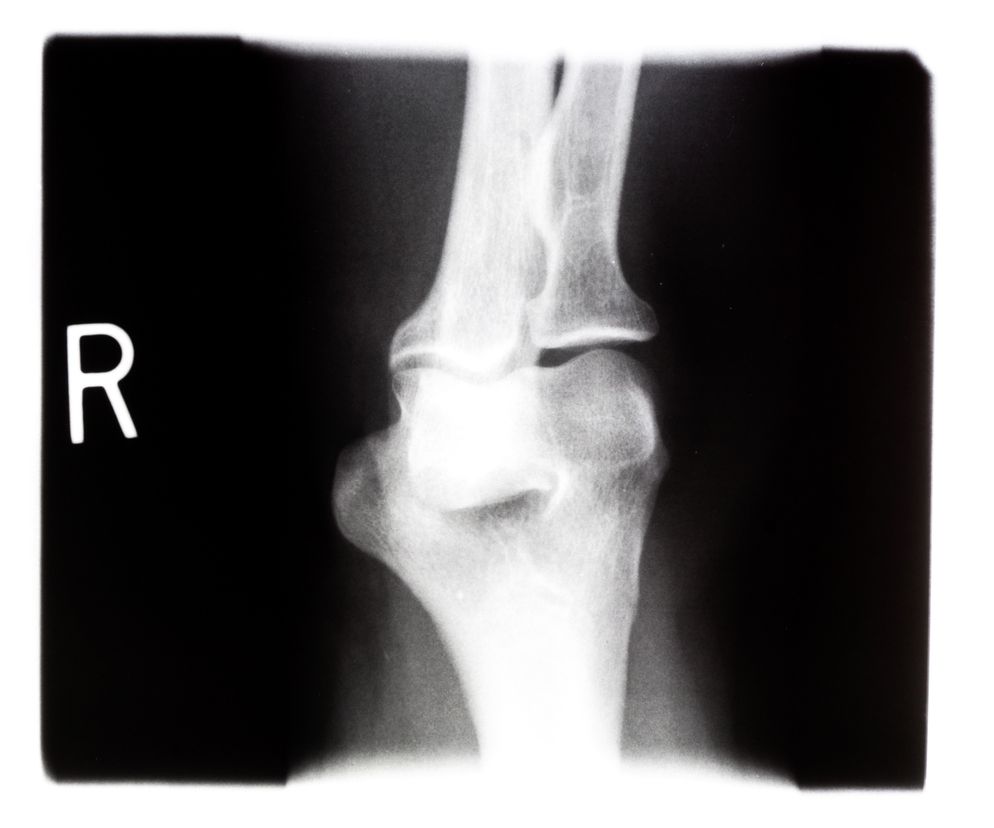

Rozpoznanie stawia się na postawie zdjęcia rentgenowskiego (RTG) chorej kości, które wykonuje się po 9 miesiącach od powstania urazu. Na zdjęciu w miejscu złamania nie widać prawidłowego zrostu kości, lecz szeroką szczelinę.